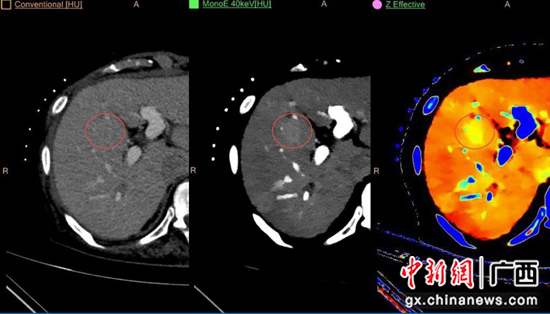

左图为常规图像,中图为单能量MonoE40KeV图,右图为原子序数图,通过单能量图和原子序数图发现的隐匿性病灶(红圈处)。南溪山医院供图 而该台CT在肿瘤病变诊断方面优势尤其明显,其低能级虚拟单能量图(virtual monoenergetic images,VMI或MonoE)能够增加异常强化病变与背景组织的对比度,有助于早期发现和诊断隐匿性病灶,提升肿瘤的良恶性鉴别能力,明确多发病灶的同源性及淋巴结转移的有无,优化肿瘤术前分期的评估,提高疗效评价准确性,协助临床实现个性化精准治疗。 此外,IQon光谱CT通过软件分析扫描部位所得到的单能量图、碘密度图、有效原子序数图等光谱数据可在骨肌系统(如关节痛风结晶、去除骨骼术后金属伪影)、神经系统(如急性脑卒中)、胸部(如低剂量CT肺癌早期筛查、肺栓塞)、泌尿系统(结石成分鉴别)、腹部及胃肠、心脑血管等系统疾病方面提供更多的诊断依据,与传统CT相比有无可比拟的优势,能明显提高疾病的早诊早治率。